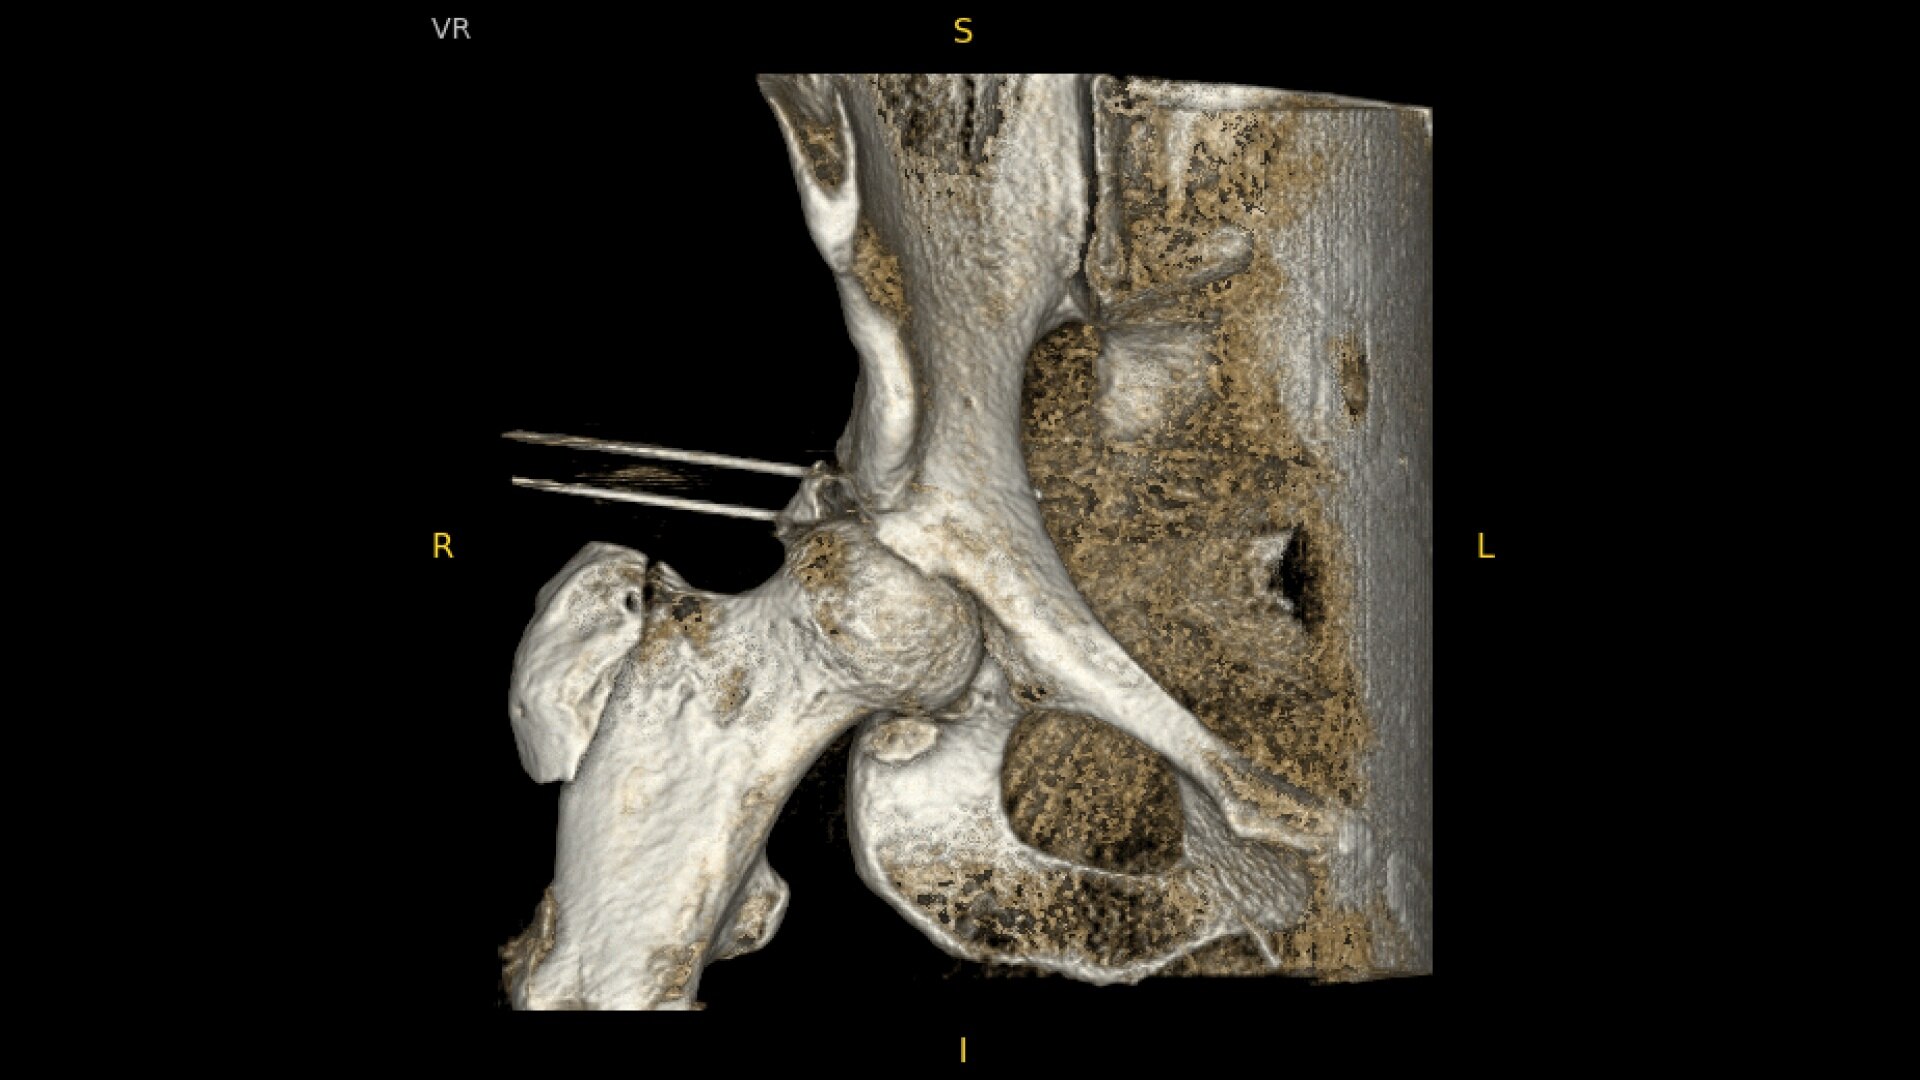

See more levels during a spinal fusion, or more of the pelvis or femur during an orthopedic procedure. With a 19 cm x 19 cm x 19 cm volume, OEC 3D captures a 67% greater volume than other 3D C-arms*.

Enhance intraoperative decision-making with visualization capabilities of Augmented Fluoroscopy in the OEC 3D Volume Viewer. Analyze five perspectives with 3D imaging tools including Multi-Oblique Mode, scrolling 512 slices, zoom, and more.